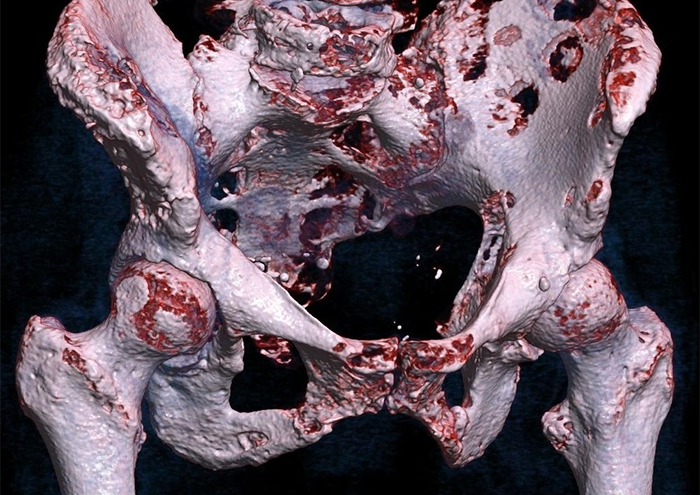

کندروسارکوم (Chondrosarcoma)

کندروسارکوم یکی از شایعترین تومورهای بدخیم لگن است که از بافت غضروفی منشأ میگیرد. این تومور عمدتاً در بزرگسالان میانسال تا مسن دیده میشود و در لگن اغلب در استخوان ایلیوم و ایسکیوم ایجاد میشود. مشخصه پاتولوژیک آن تولید ماتریکس غضروفی است و به زیرنوعهای معمولی، شفافسلولی و مسنژیمی تقسیم میشود که هر کدام ویژگی رفتاری متفاوتی دارند.

متاسفانه افرادی که دچار این تومور میشوند، علائم اولیهای مانند درد مداوم، تورم و محدودیت حرکتی مفصل لگن را تجربه میکنند که به دلیل غیراختصاصی بودن، تشخیص ممکن است به تأخیر بیفتد. از منظر درمان، جراحی با حذف کامل تومور (حاشیه منفی) اصلیترین روش است، زیرا کندروسارکوم نسبت به شیمیدرمانی و پرتودرمانی مقاومت بیشتری دارد. پیشآگهی به درجه تومور و میزان نفوذ به بافت نرم وابسته است.